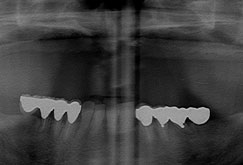

3. 歯が1本もなくても

Cさんの上の顎には1本も歯がなく、長年総入れ歯を使っていました。

Cさんの上の顎には1本も歯がなく、長年総入れ歯を使っていました。

Cさんの奥さんは、Cさんほど歯は悪くなかったのですが、部分的に歯を失ってしまいました。Cさんの奥さんは私のところで、インプラント治療を受けて丈夫な歯を歯を手にいれました。そこでCさんは、一大決心をしてインプラントで総入れ歯からの脱出を決意したのです。

Cさんの上の顎は長年の入れ歯生活のせいで、かなり骨が少なくなっていました。

特に前歯の骨は全くないといって状態でした。

特に前歯の骨は全くないといって状態でした。

さらに奥歯はサイナスという空洞が大きくやはり骨がほとんどない状態でした。はっきり言って超難症例です。

日本中の歯科医院を廻っても誰がこの難症例を治せるでしょうか?

Cさんは辛抱強く私の治療についてきてくれました。

骨が少ないので、期間はある程度かかりましたが、その間に私ともスタッフともとても仲良くなって楽しそうに通院していただきました。

奇麗な歯を手に入れたCさんは総入れ歯から脱出をしたのでした。